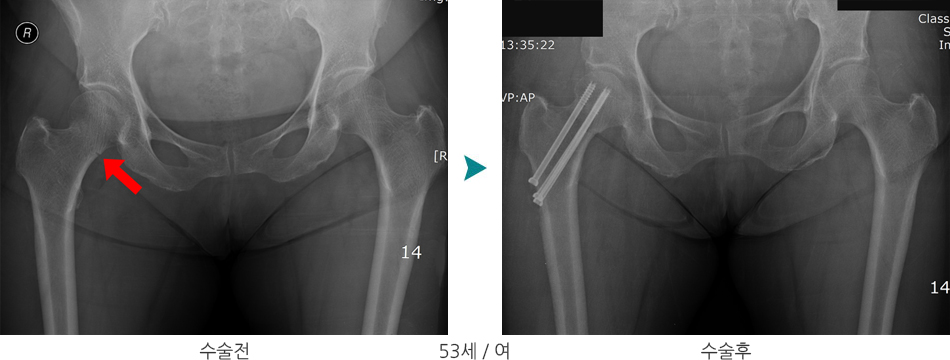

단순 방사선 사진으로 확인이 가능하며, 이외에도 전산화 단층 촬영으로 골절 형태 파악에 도움이 될 수 있습니다.

골절형태와 위치에 따라 적절한 치료방법을 선택하며 소아, 중년, 노년에 따라서 정복과 고정하는 방법이 다를 수 있습니다. 노년층의 경우 경부골절에서 골유합이 어렵기 때문에 인공관절 치환술이 많이 시행됩니다.